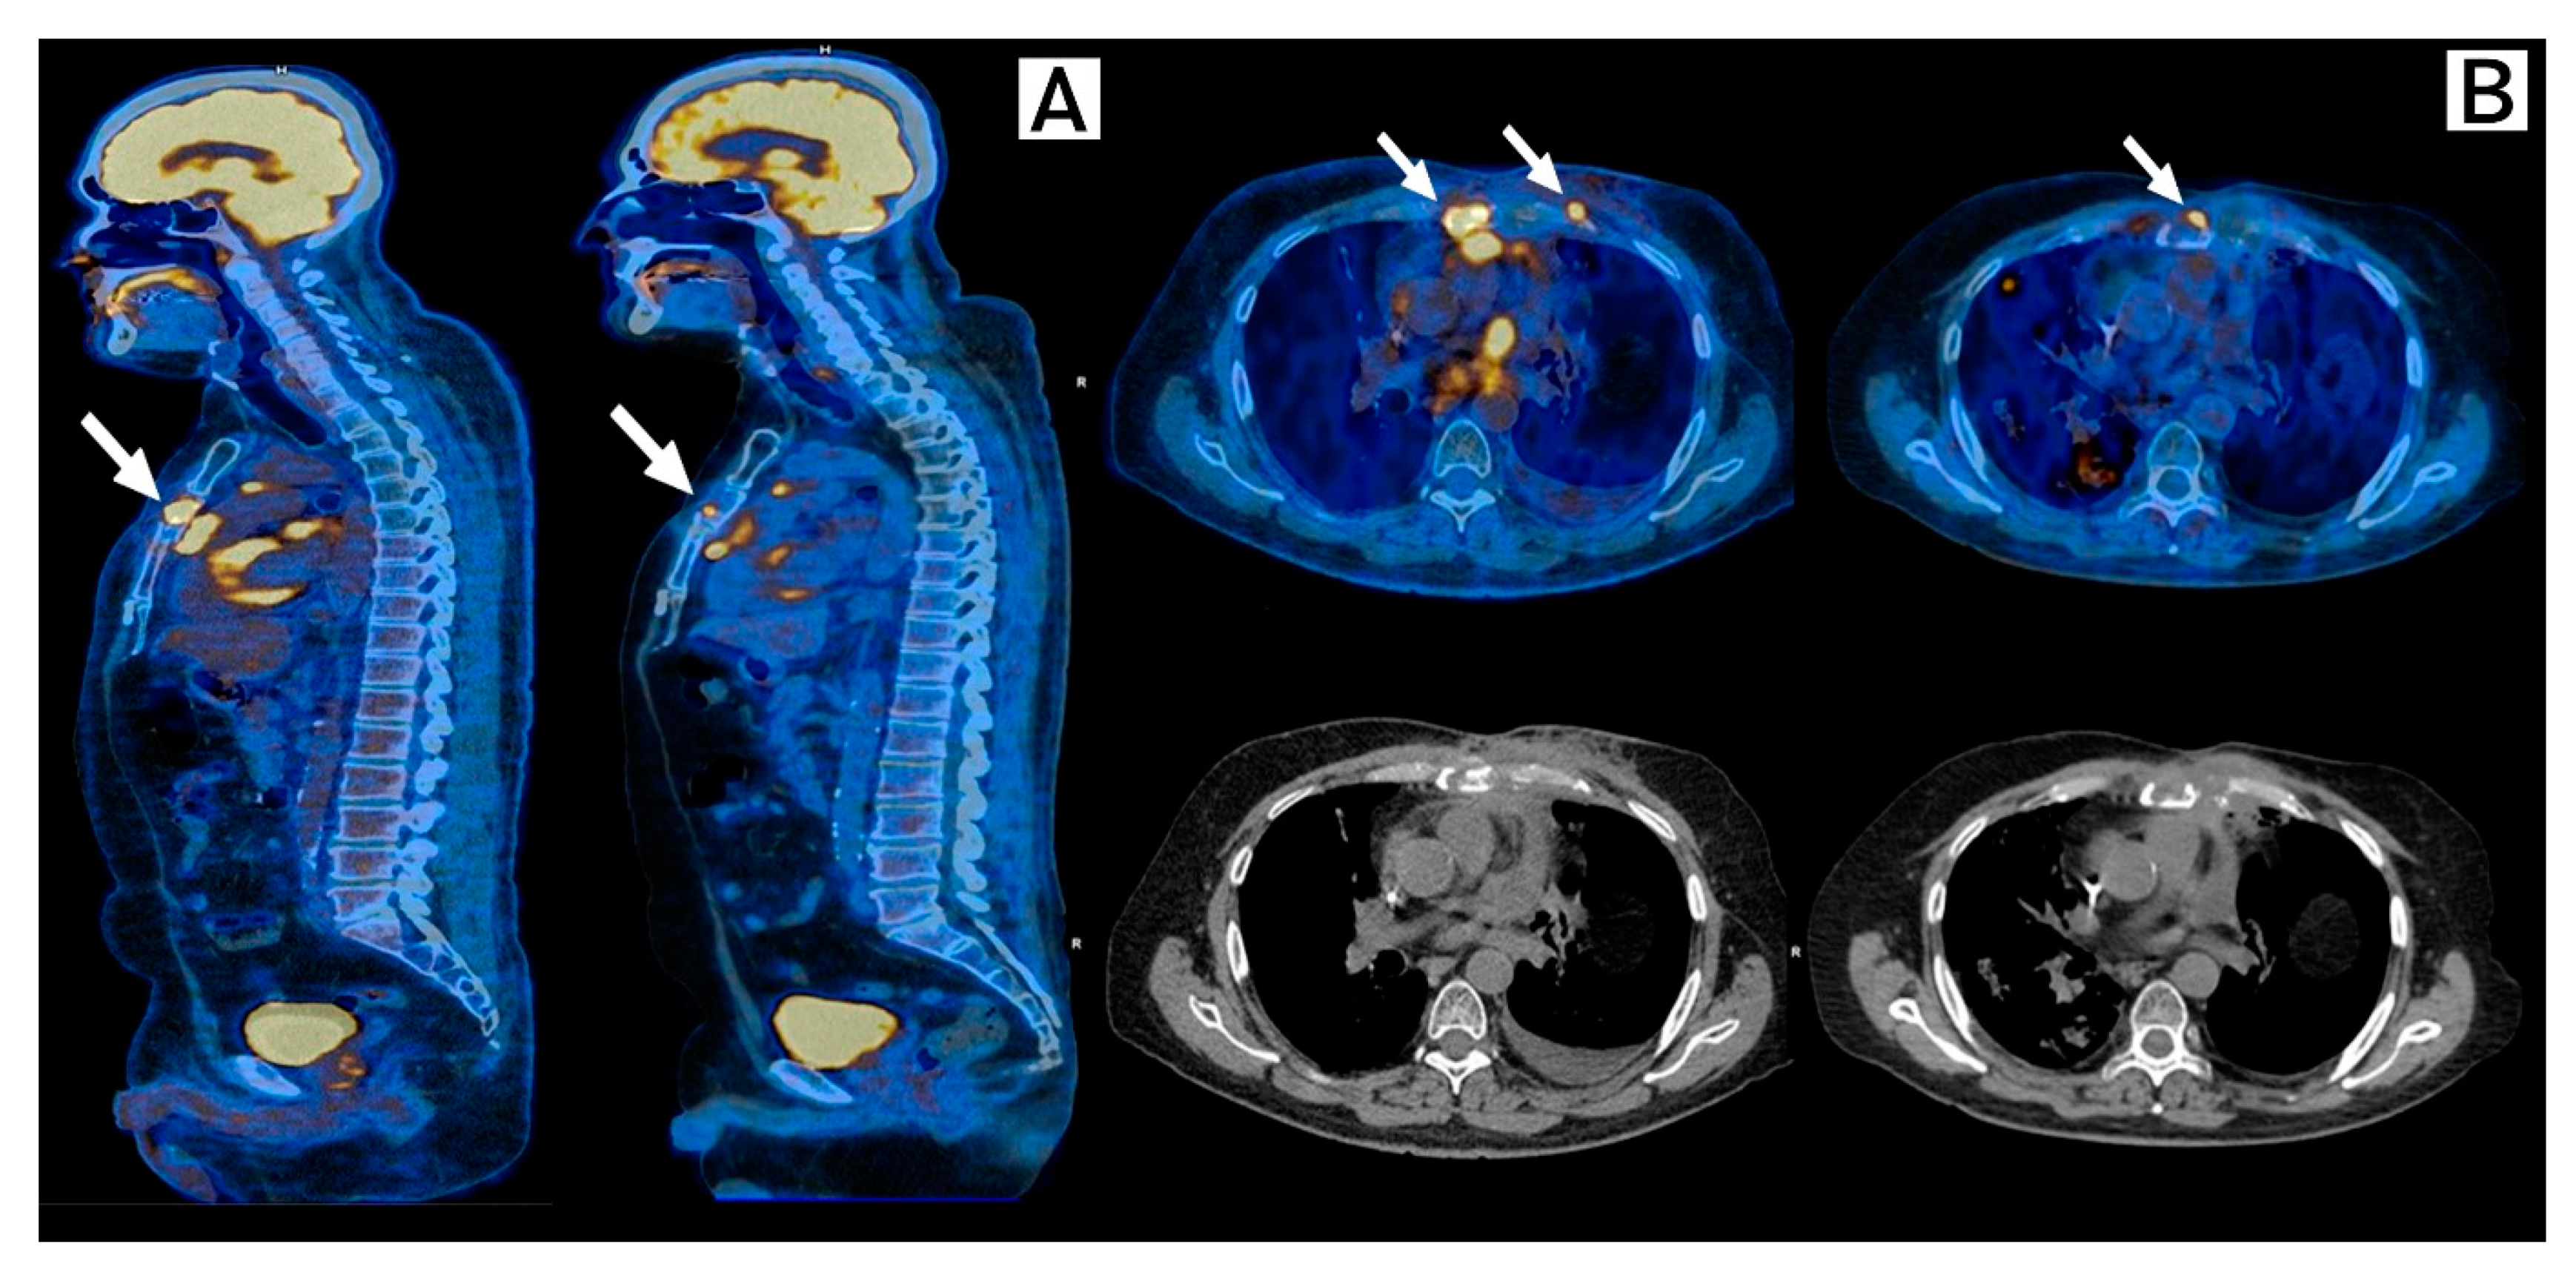

2. Case Description